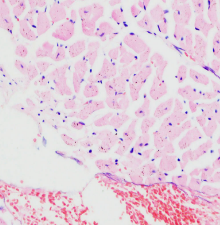

产品名称:苏木素伊红混合染色液 Hematoxylin-Eosin (HE) Stain Solution

主要用于细胞涂片染色,尤其适用妇科细胞染色和骨髓细胞染色。苏木素伊红混合在一起,染色只需一步